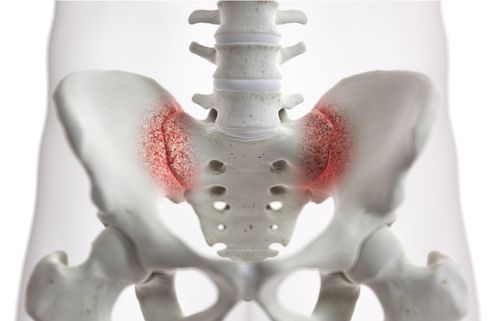

Sacroiliac Joint Pain

Sacroiliac Joint Injection